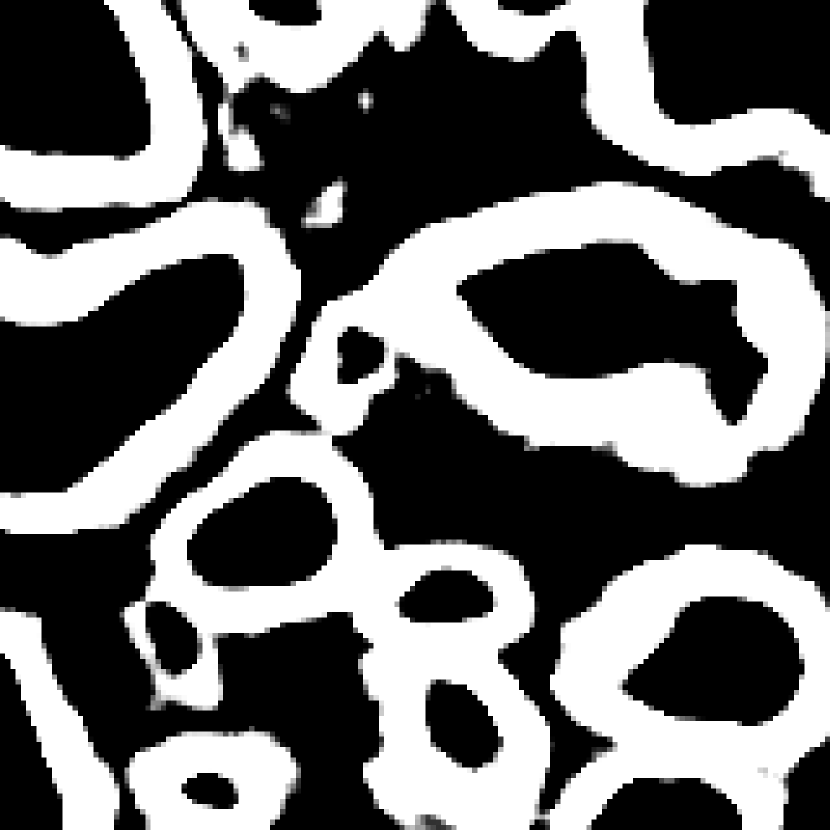

Fig. 3 shows two image examples, their ground-truth masks, and the final segmentations generated by competing models. Comparing with U-Net, Res-Seg based models generally have fewer false positives. Comparing with Res-Seg-Net, Res-Seg-Net and Res-Seg-Net both generate cleaner outputs, which can serve as an evidence that hierarchical refinings are effective in improving segmentations in both accuracy and robustness. These effects can be clearly seen within the areas highlighted with green boxes.

We fed Res-Seg-Net with the patch in the first row of Fig. 3, and output their segmentations maps of each layer in Fig. 4. The segmentation refining process is evident, as more and more details are added to the finer outputs. The low resolution segmentations tend to catch the primary shapes of the target objects. Moving upwards, they not only provide guidance for fine-resolution labelings to capture more details, but also set up certain guard to reduce the appearance of noisy spots.